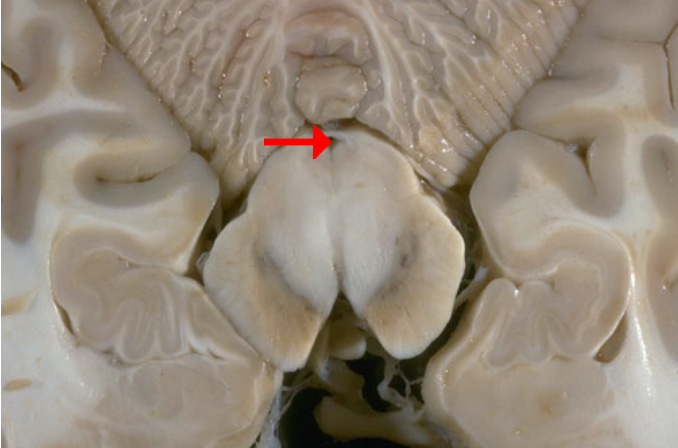

Label this brain structure

Septum pellucidum

Label this brain structure

Optic chiasm

Label this brain structure

Cingulate gyrus

Label this brain structure

Substantia nigra

Label this brain structure

Optic tract

Name this brain structure

Hippocampus